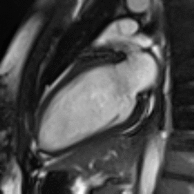

Heart function using cine imaging

Functional and structural information is acquired using bSSFP cine sequences. These are usually retrospectively-gated and have intrinsically high contrast in cardiac imaging due to the relatively high T2:T1 ratio of blood compared to myocardium. Images are typically planned sequentially to achieve the standard cardiac planes used for assessment. Turbulent flow causes dephasing and signal loss allowing valvular disease to be qualitatively appreciated. The left ventricular short axis cines are acquired from base to apex and are used for quantifying end-diastolic and end-systolic volumes, as well as myocardial mass. Tagging sequences excite a grid pattern that deforms with cardiac contraction allowing strain to be assessed.

Example CMR images. In sequence: a coronal localiser, 2 chamber cine, 4 chamber cine, left ventricular short axis cine, and tagged image. Additional cines of the left ventricular outflow tract and aortic valve may also be acquired.